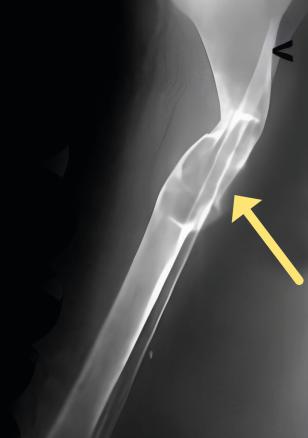

Image radiologique de tumeur brune. Lésion ostéolytique soufflante pouvant entraîner une fracture pathologique.